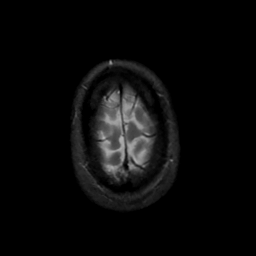

MR Study #13, May 19, 1991 -- Slice #46

[Home][Help][Clinical][Tour 1][Tour 2] Slice 46